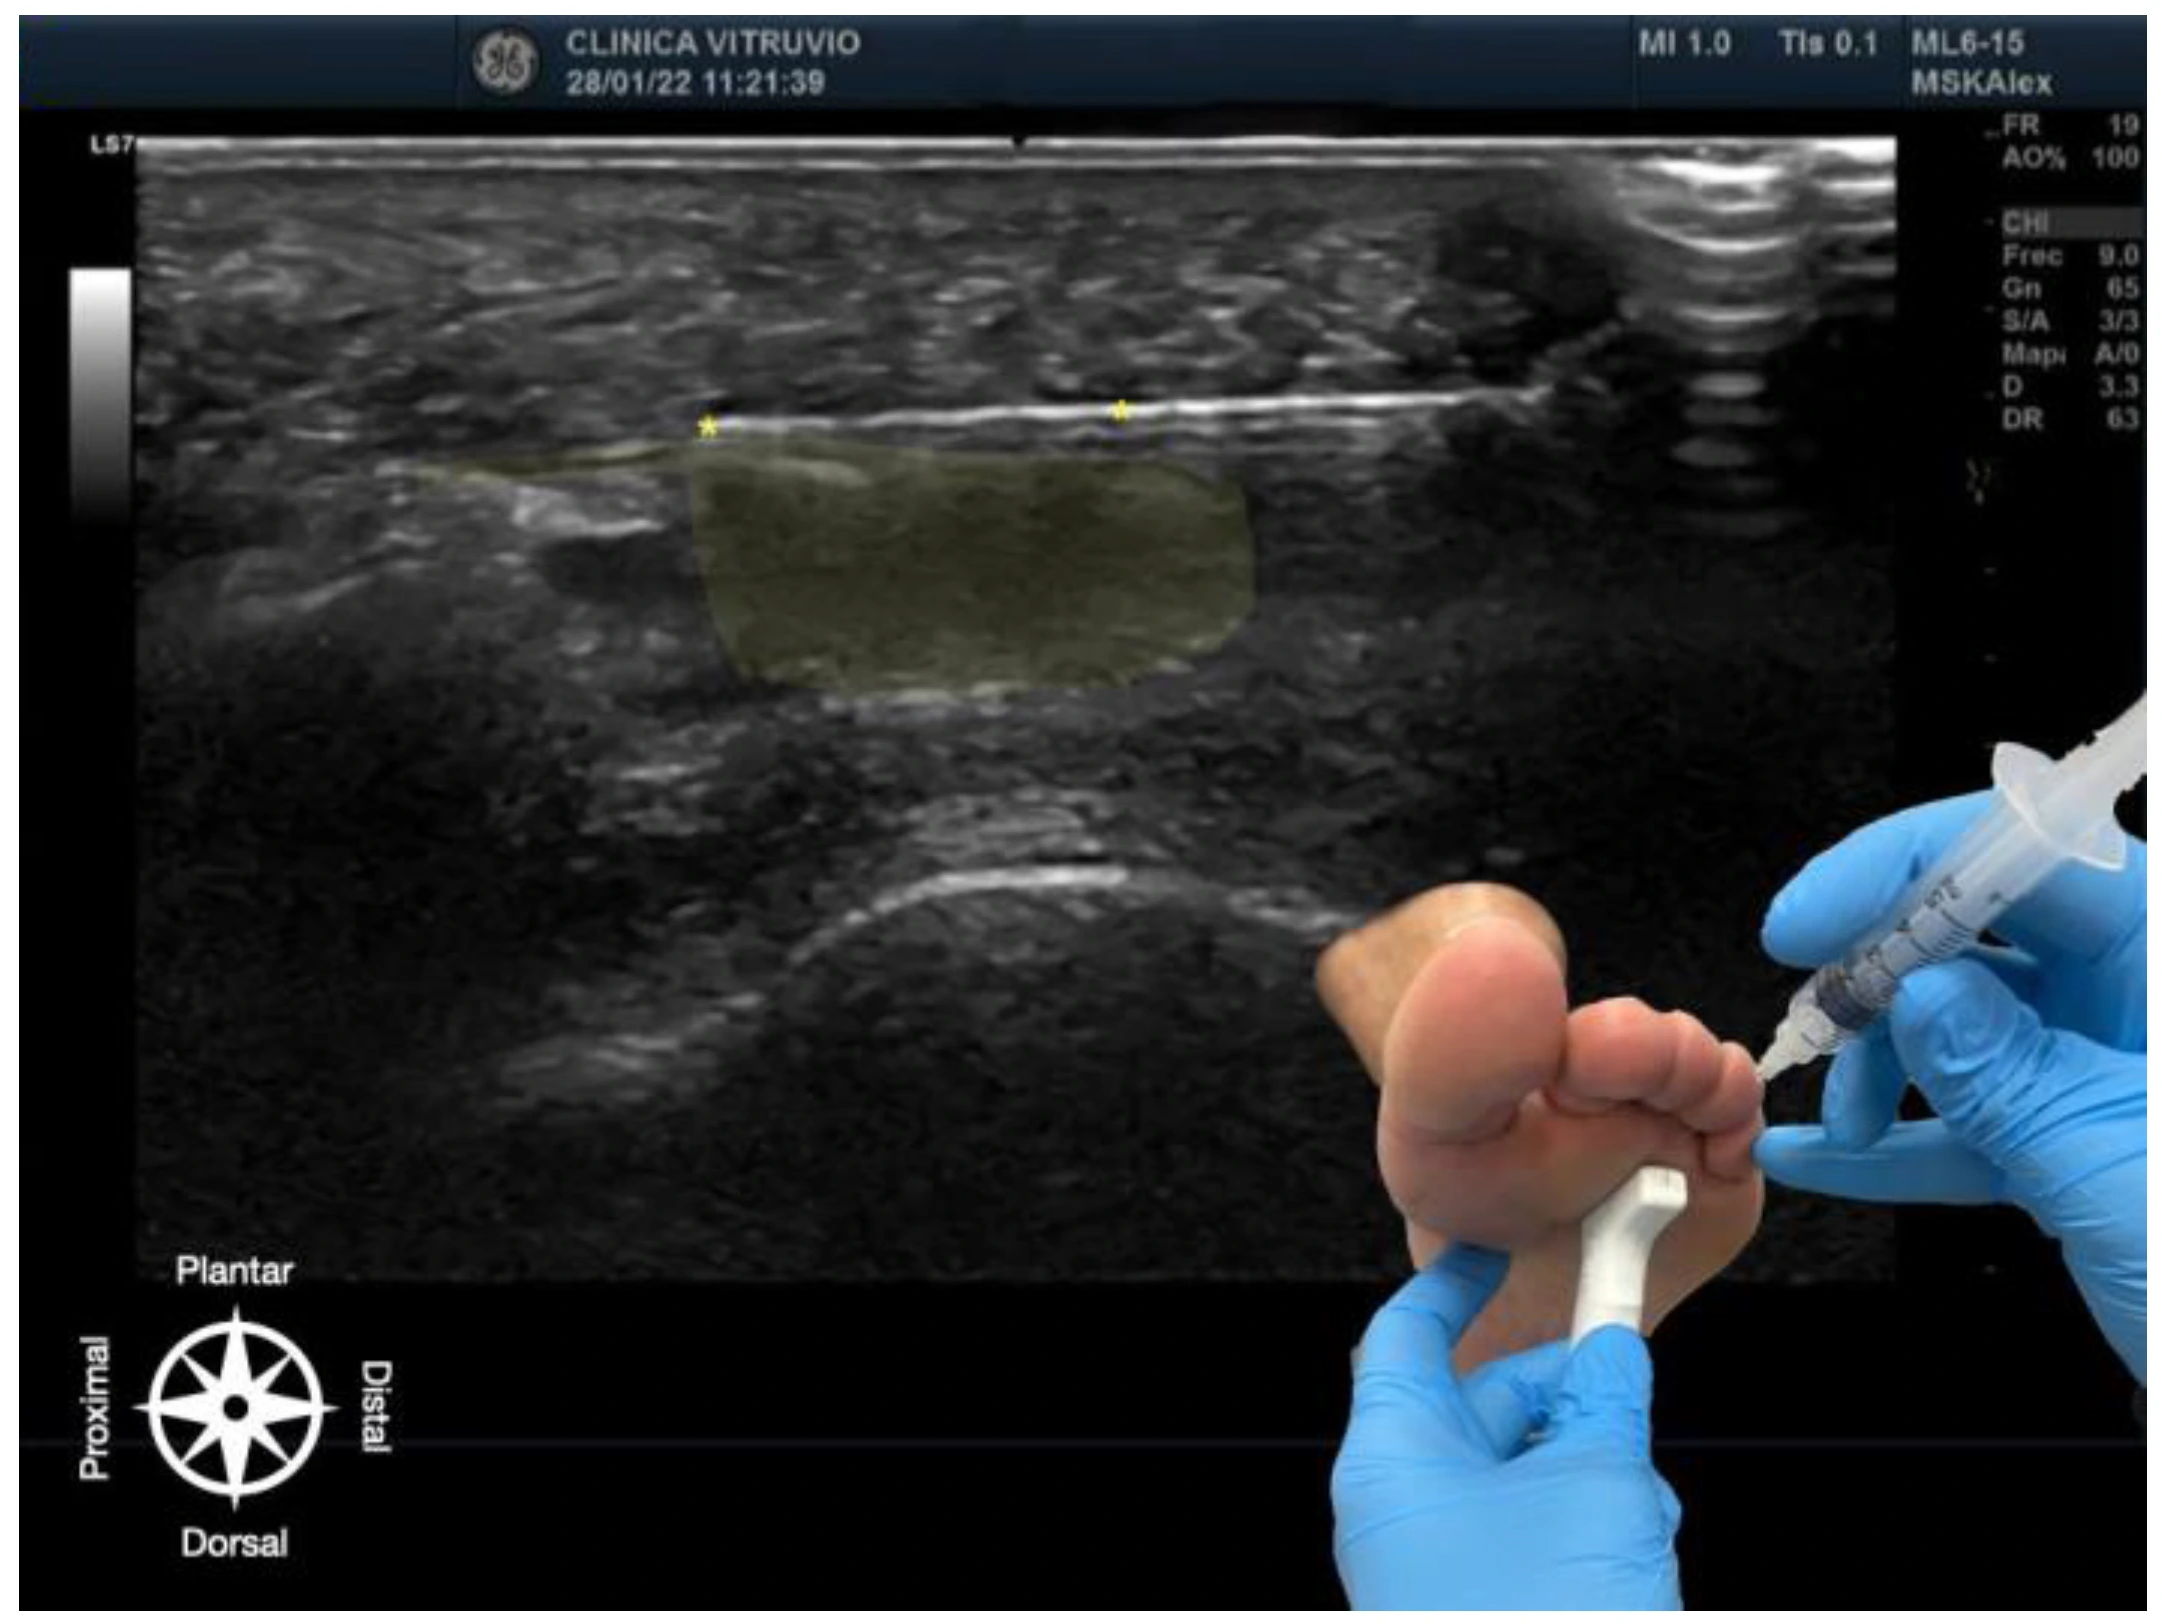

The procedure was performed using high-resolution ultrasound (10–15 MHz linear transducer) under real-time guidance (Figure 1 and Figure 2), following the selective infiltration protocol described by Ruiz Santiago et al. for Morton’s neuroma [3]. Three injections were performed on each anatomical specimen: 1—metatarsophalangeal joint of the third ray (3rd MTP joint), 2—metatarsophalangeal joint of the fourth ray (4th MTP joint), and 3—intermetatarsal space between the third and fourth rays (IM space).

Figure 1. Ultrasound-guided intra-articular infiltration of the metatarsophalangeal joint (Dorsal view). The joint capsule (dorsal recess) is highlighted in green, showing the needle, marked with an asterisk (*) in yellow, inside the articular space. In the lower right corner, the dorsal approach with probe and needle placement is displayed. The anatomical orientation diagram indicates the proximal–distal and dorsal–plantar axes.